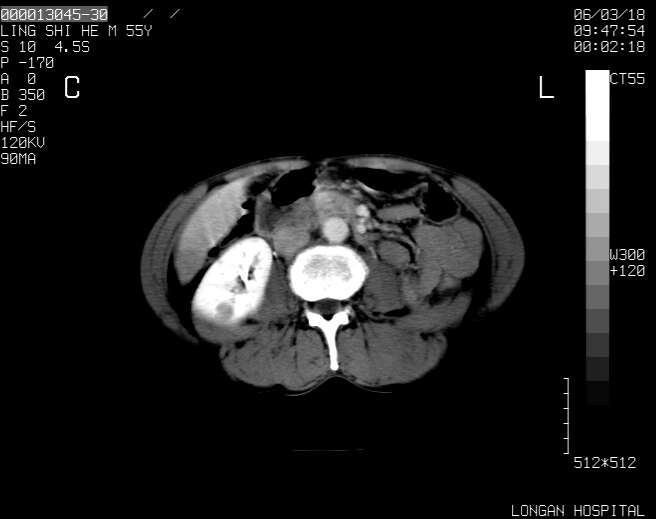

以下是引用guzhongliangddd在2006-3-21 22:13:00的发言:[br]病灶主要位于肝右叶的后份,内见异常血管,门脉主干及右支受侵{提示有癌栓形成},门腔间隙内见增大淋巴结。肝左叶内未见异常。

以下是引用zhuxinli在2006-3-22 1:23:00的发言:[br][br] 病灶主要位于肝右叶的后份,内见异常血管 .门脉右支截断,右叶前段早期强化(考虑动静脉漏),腹膜后肿大淋巴结,病灶逐渐强化,考虑为胆管细胞癌[br]